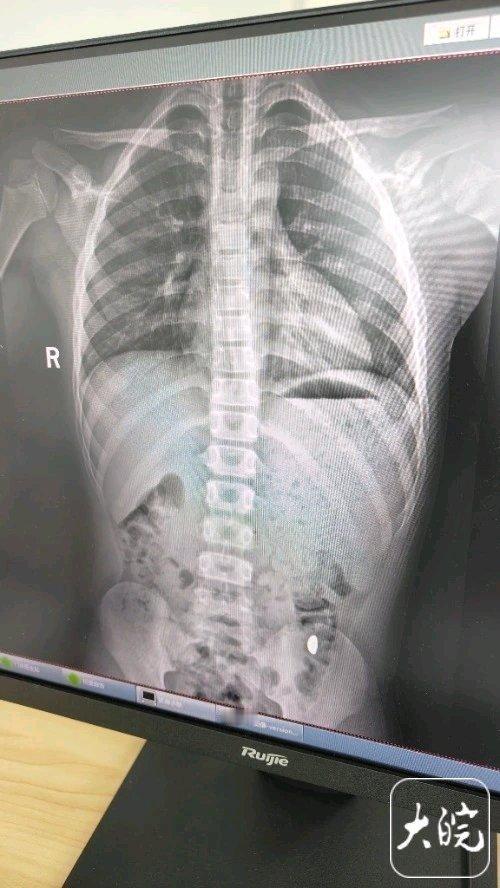

现在的熊孩子真是让人又气又笑。江苏昆山的纪女士就遭遇了这样的闹心事。10月17日她花万元网购了10克重的金豆子,21日或22日孩子拿到屋里玩,竟为了锻炼舌头力量把金豆子吞了。 纪女士起初还以为孩子开玩笑,确认后哭笑不得。想起侄女曾吞硬币能排出,她就没太担心,还天天叮嘱孩子别在外面拉屎,说这屎有点贵。等了5天没找到金豆,才带孩子去医院,结果上午去下午金豆就排出了。这事在社交平台引50多万人围观,也提醒大家得看好家里的贵重物品啊。